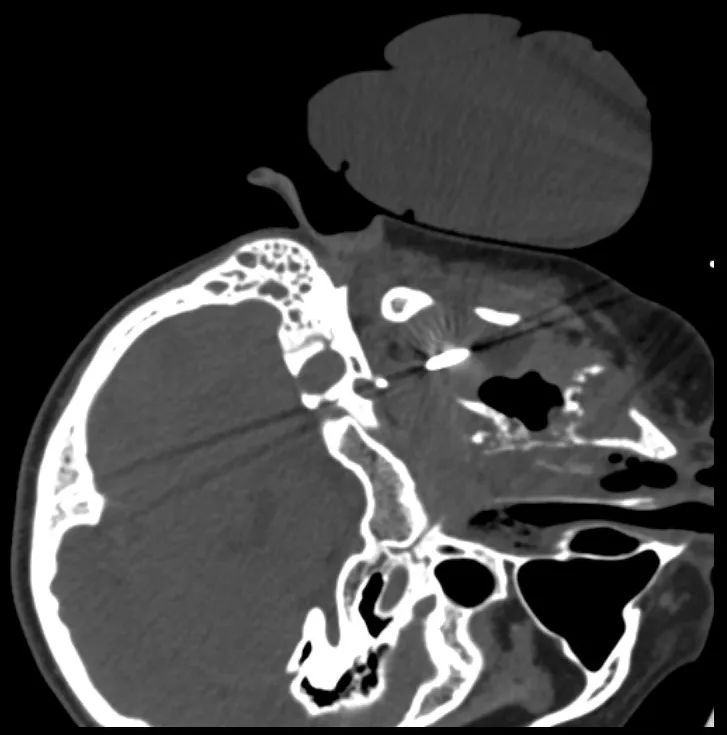

硬腭癌复发冷冻消融术治疗中的医学影像图片